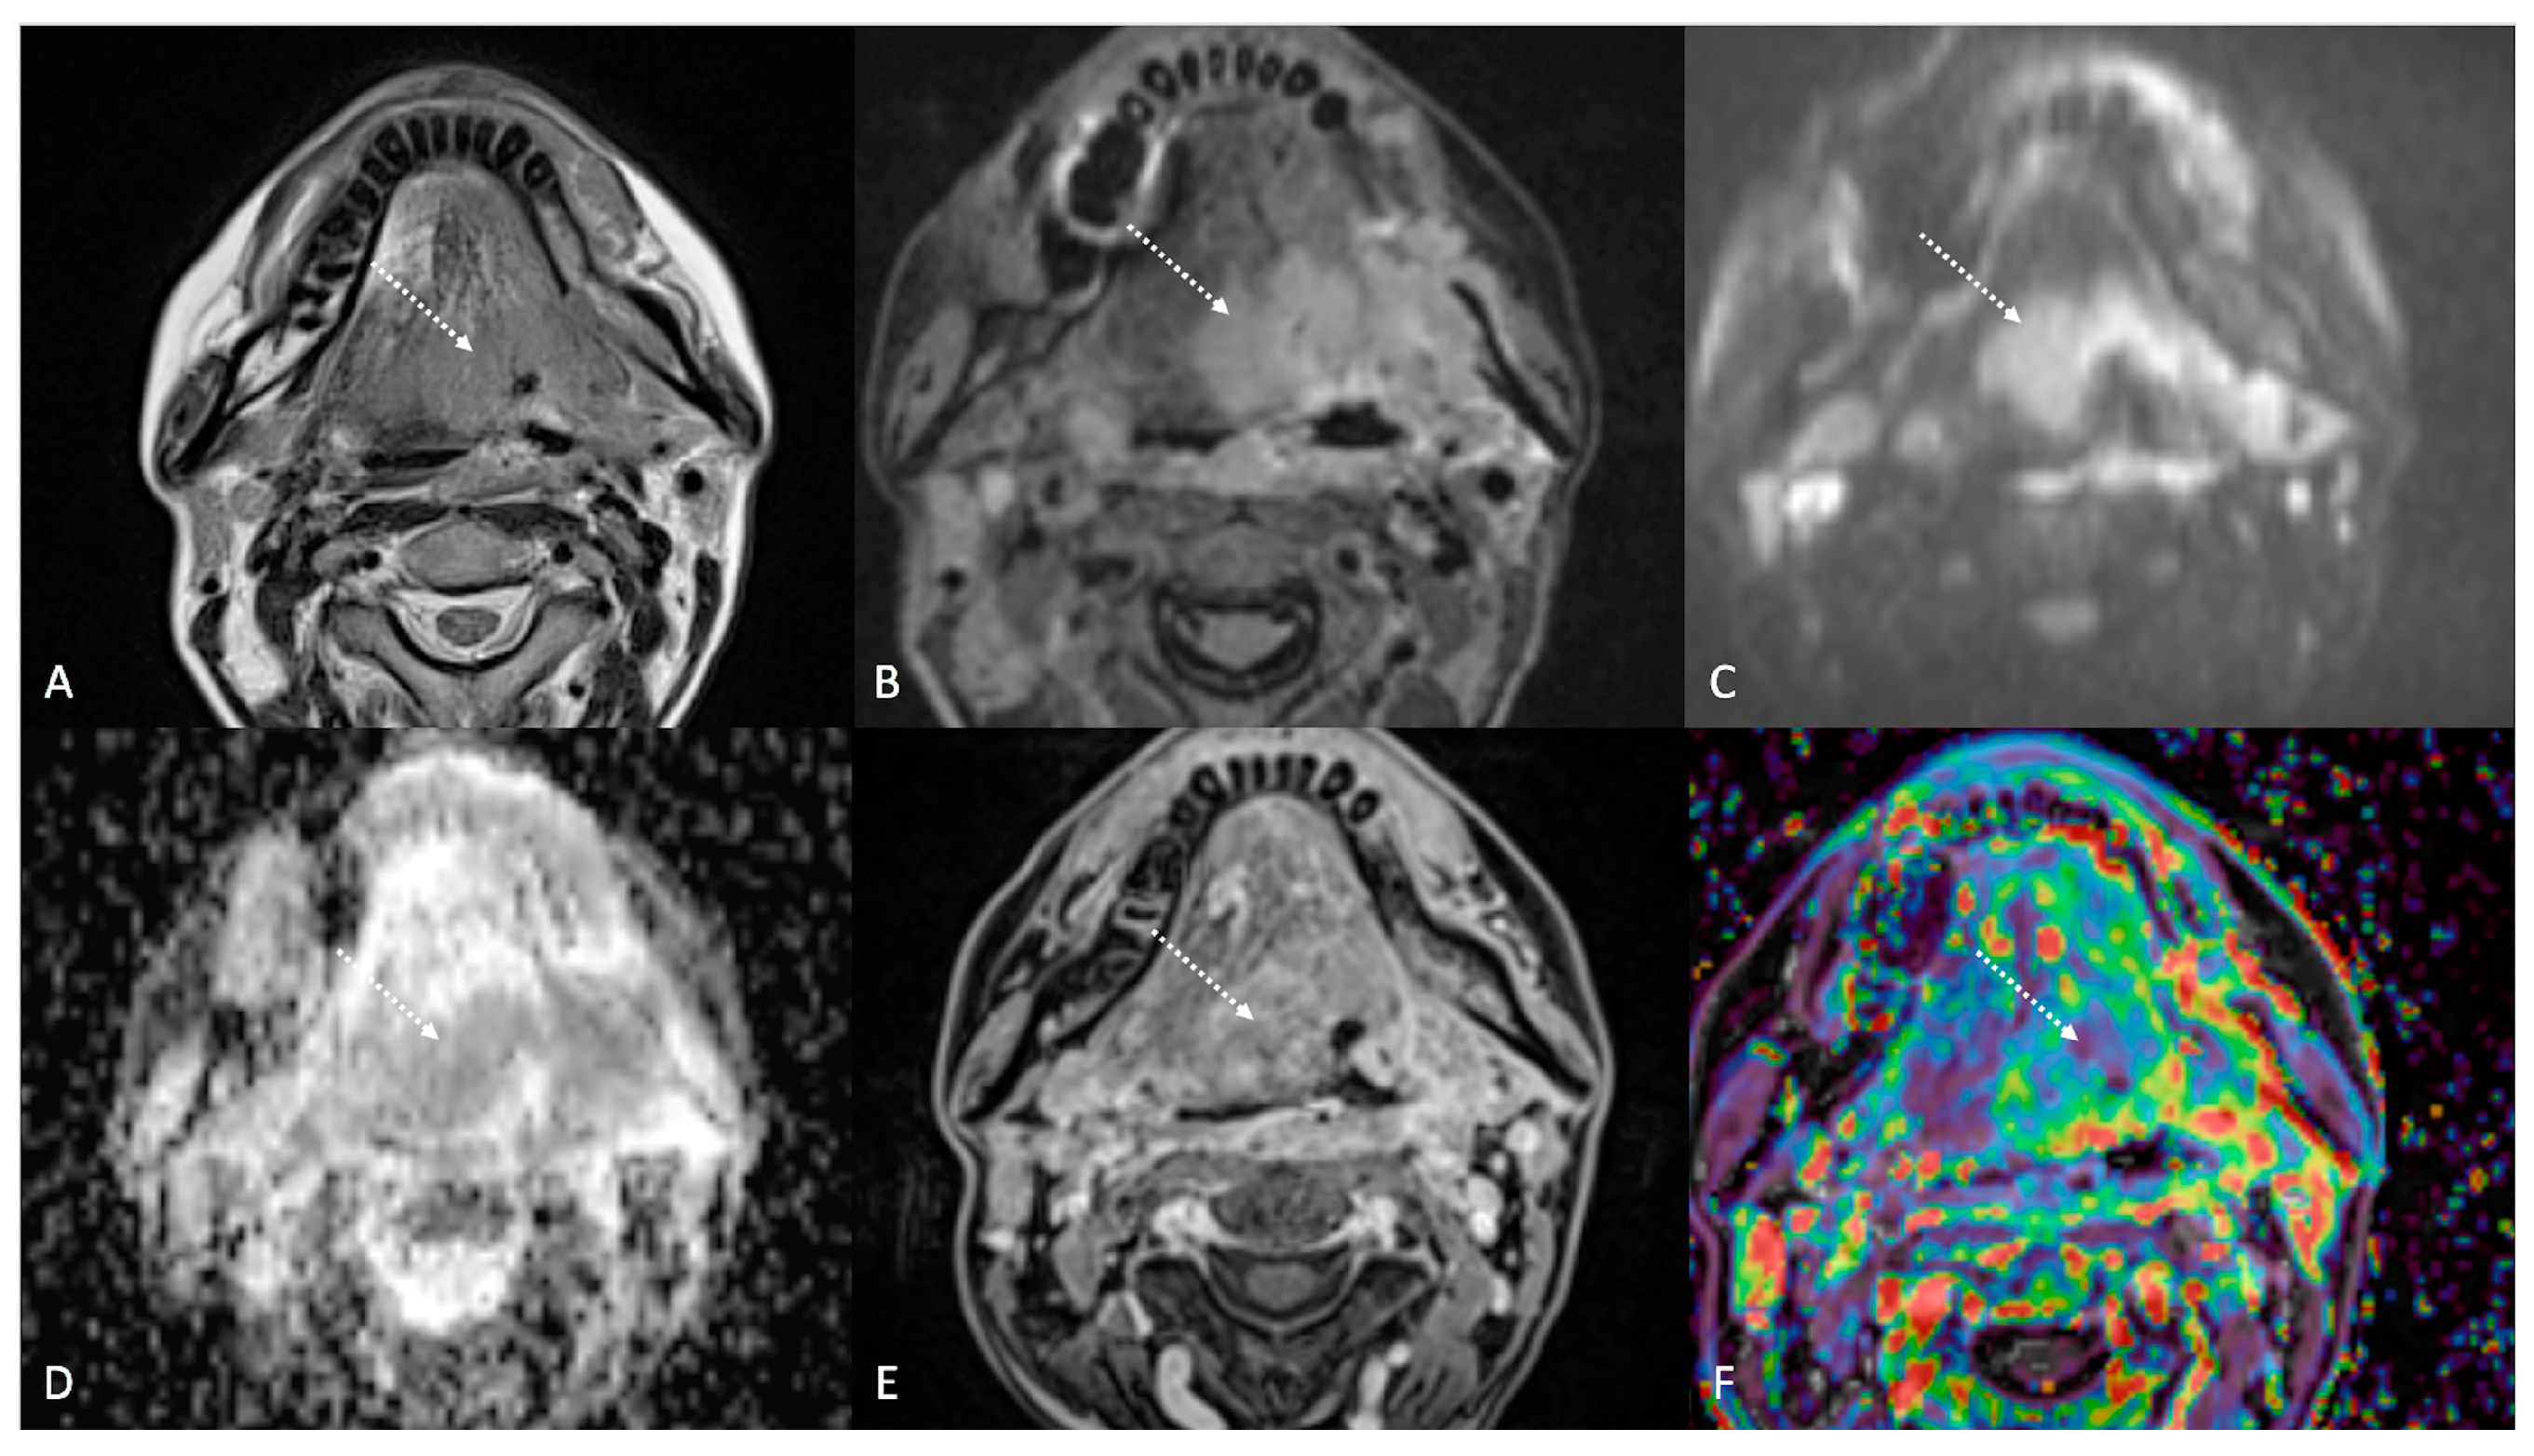

Figure 5.

Post-treatment magnetic resonance imaging (MRI) of a 47-year-old female patient with human-papillomavirus-negative carcinoma of the left palatine tonsil with ipsilateral lymph node metastasis (T4aN1) and buccal space and mandibular invasion, recently treated (4 months before) with chemoradiotherapy (CRT). Early post-treatment MRI showed tumor progression with wide extension to the extrinsic muscles of the contralateral tongue (maximum tumor thickness 45 mm). Post-CRT tumor residual/relapse disease (white striped arrows) showed moderately high (intermediate) T2-weighted signal intensity (A,B), high signal on diffusion-weighted b800 imaging (C), low apparent diffusion coefficient value (0.79 × 10−3 mm2/s, (D), and moderate enhancement after gadolinium contrast injection (E). K(trans) value of the tumor (56.24 × 10−3 min) decreased on dynamic contrast enhancement-perfusion weighted imaging (F), compared to pre-treatment MRI (117.63 × 10−3 min). However, the ratio between K(trans) values of the primitive tumor and residual tissue after CRT, standardized with respect to K(trans) value of the ipsilateral trapezius (K(trans)post/pre/muscle), was 1.14. These findings suggested little or no reduction in tumor neoangiogenesis after CRT.